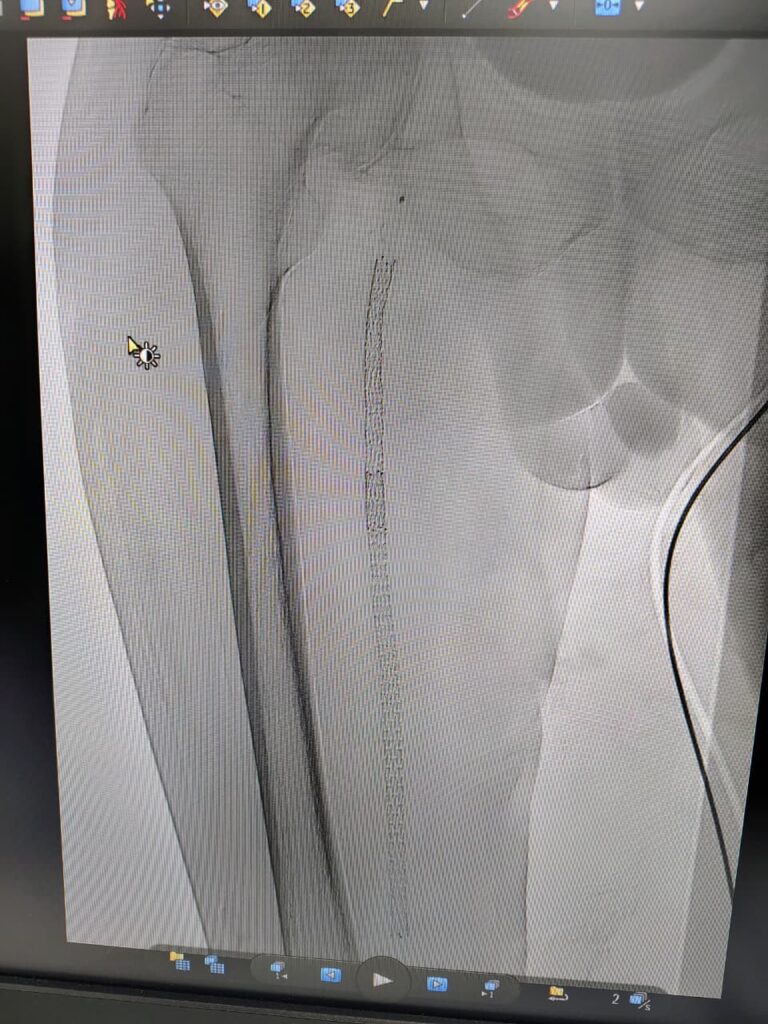

Case 3

A Minimally invasive procedure to open the blocked blood vessels in the lower limbs by Angioplasty